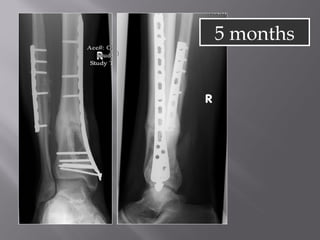

5 months